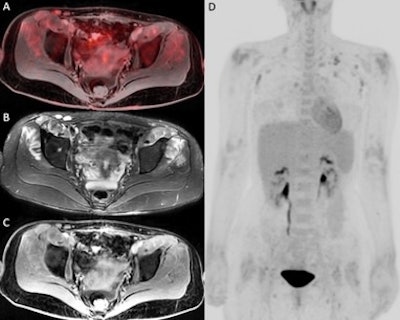

In an example image from the study, F-18 FDG-PET/MRI fusion image (A) and PET 3D image (D) show a moderately increased FDG uptake in muscles around hip joints. T2 IDEAL WATER image (B) shows increased T2 signal; LAVA WATER (C) image shows mild enhancement in these muscles. Findings were suspicious of myositis, which was histopathologically confirmed. Image courtesy of the European Journal of Radiology.